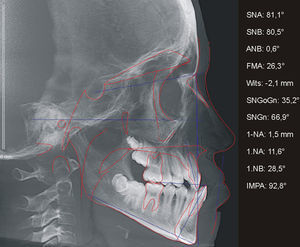

O histórico de cirurgias do paciente B, sexo masculino, se assemelha ao da paciente anteriormente descrito, assim como os efeitos sobre sua maxila e suas características relativas ao perfil facial, padrão esquelético e dentário (figs. 5 e 6). Igualmente acompanhado pelo CENTRARE, concordou‐se em iniciar a ERM aos 12 anos. Realizados exames clínicos e TCFC, observou‐se: tendência a uma má oclusão esquelética de Classe III (ANB=0,6°; Wits=–2,1mm), maxila bem posicionada em relação à base do crânio (SNA=81,1°), incisivos superiores retroposicionados e retroinclinados (1.NA=‐1,5mm; 1.NA=11,6°) e incisivos inferiores bem posicionados na base óssea (1.NB=28,5 graus; IMPA=92,8 graus) (fig. 7). Diante da necessidade de expansão limitada à região anterior, foi instalado em JFRL o disjuntor mini‐Hyrax invertido com BTP11. Confeccionado com um mini parafuso (Variety Expander, DynaFlex, Saint Ann, Missouri, EUA) posicionado na região mais anterior possível do palato. Extensões provenientes do parafuso (fio 1,4mm) contornaram a superfície palatina dos caninos, passando pelas bandas nos primeiros pré‐molares e chegando até à superfície palatina dos segundos pré‐molares. Além disso, uma BTP (fio 0,9mm) foi soldada em bandas nos primeiros molares permanentes (fig. 8).